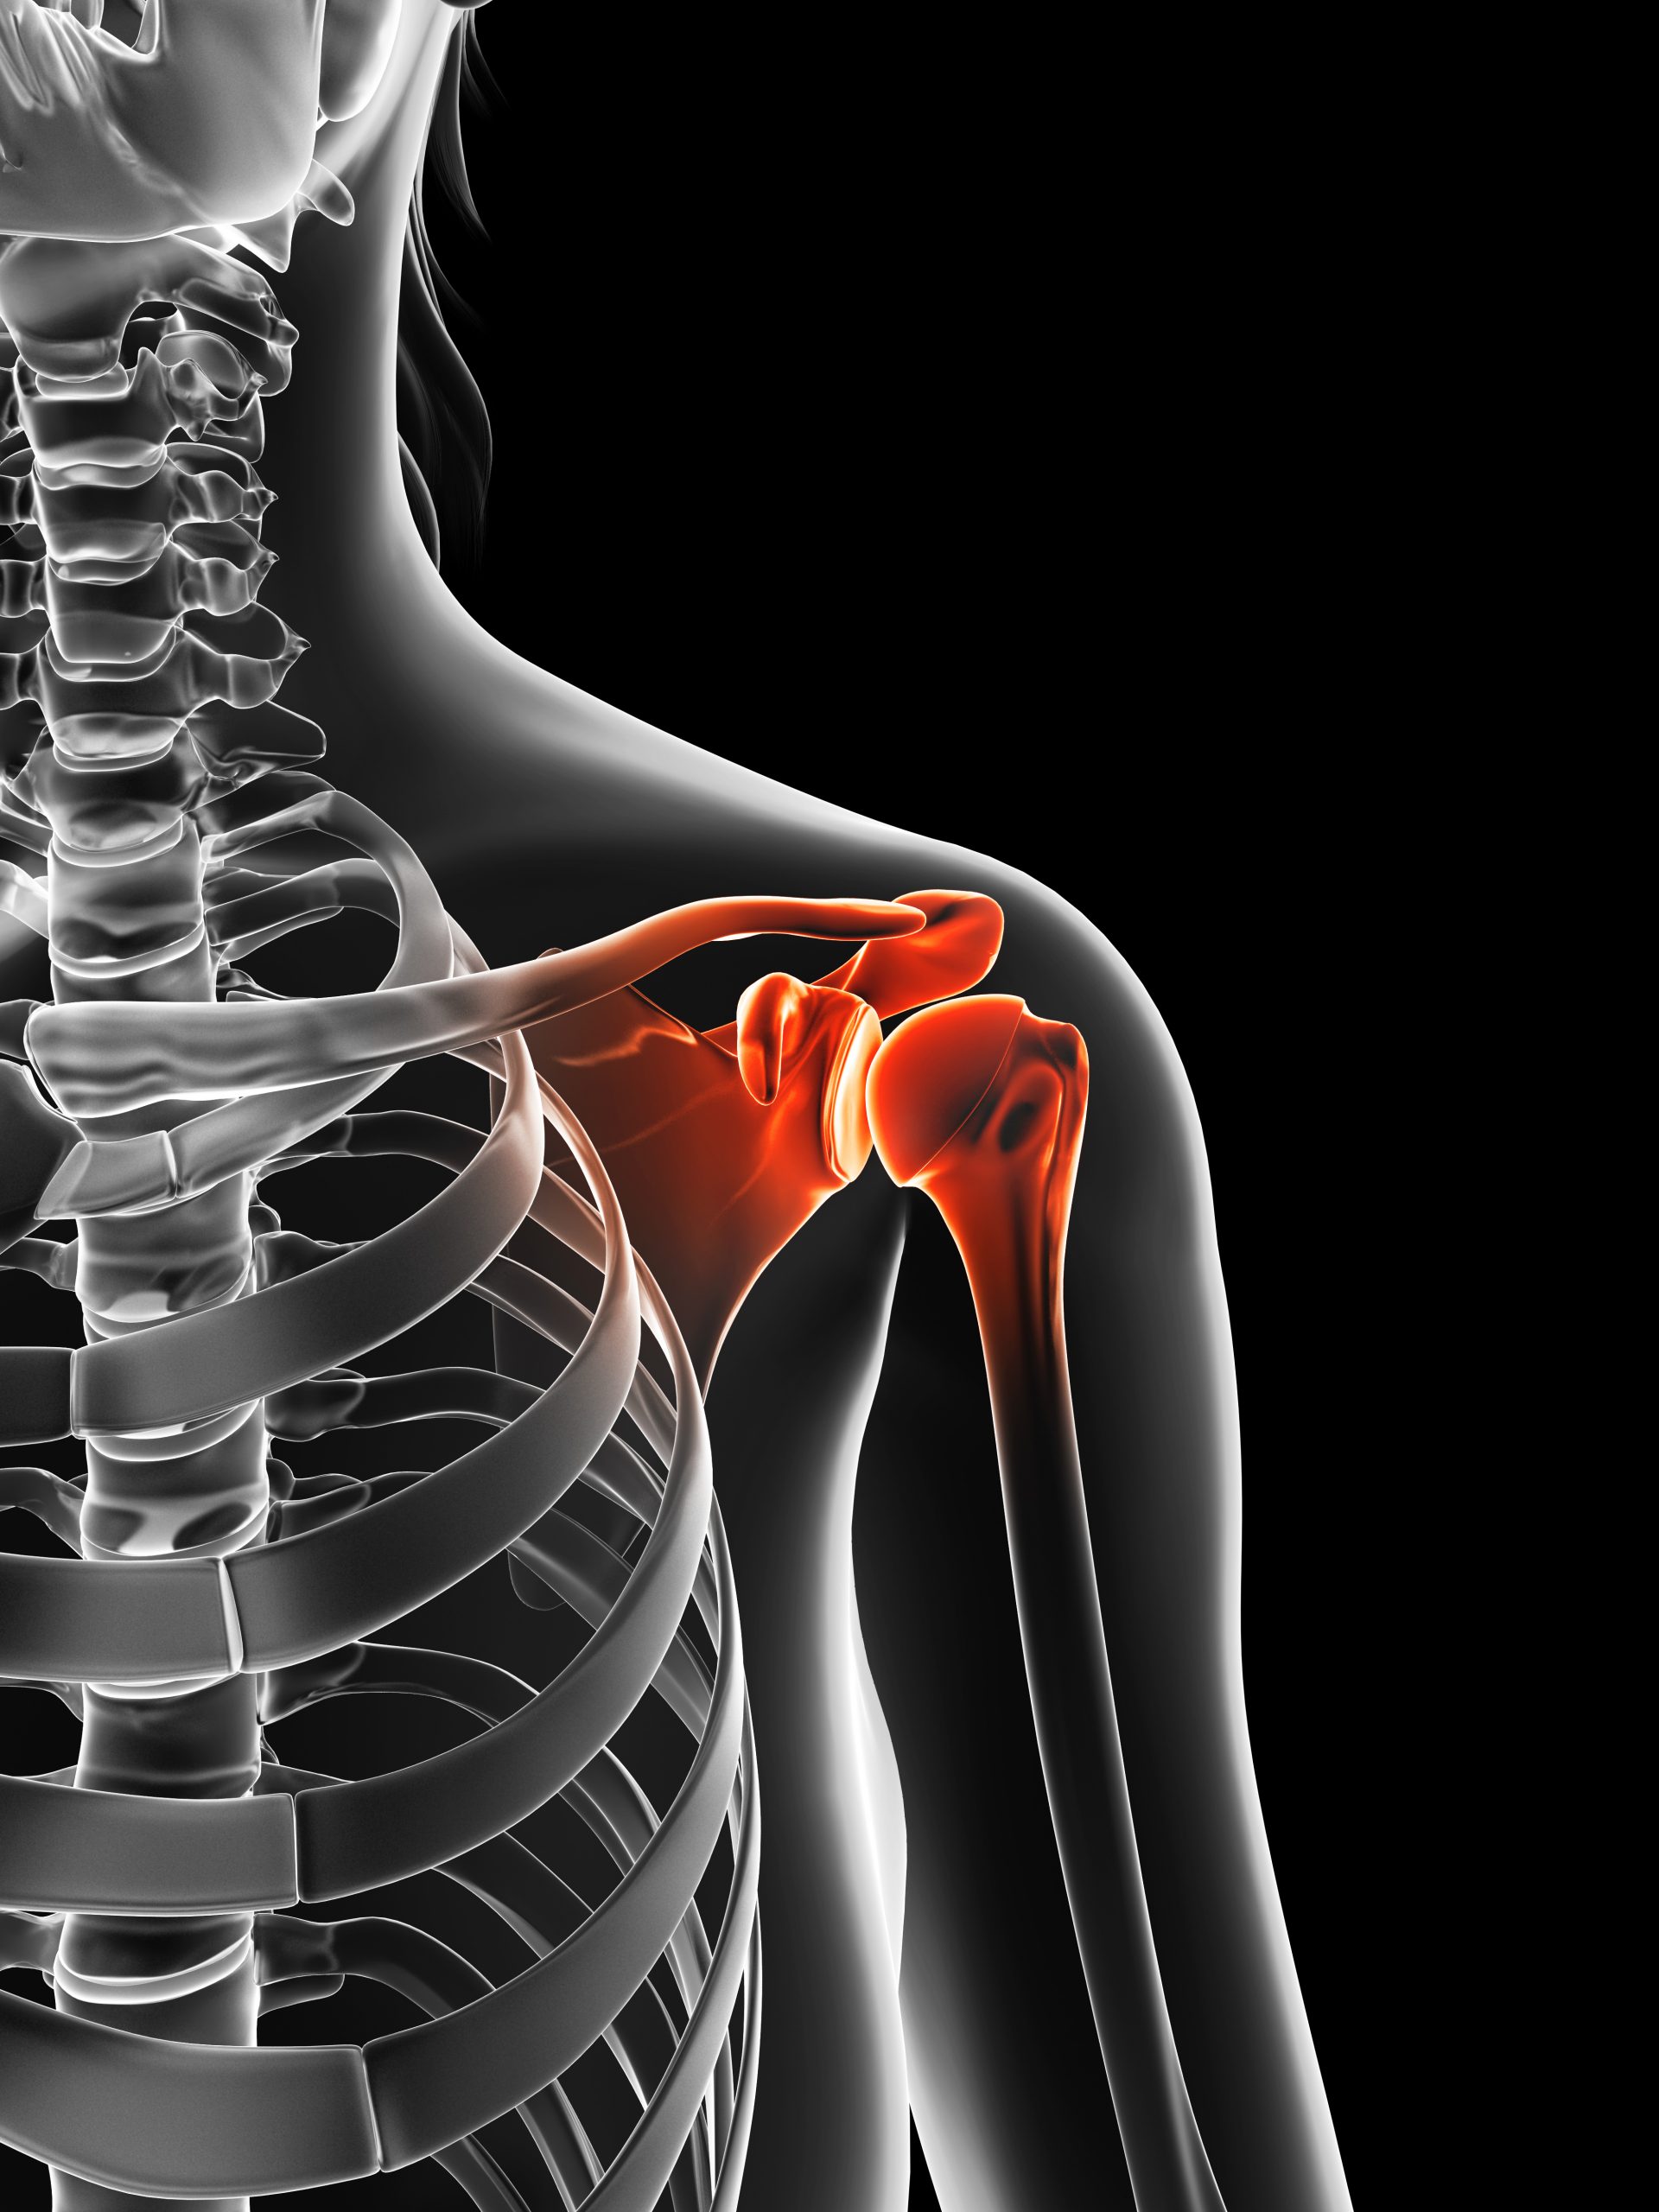

Dislocated shoulder

A dislocated shoulder is an injury in which your upper arm bone pops out of the cup-shaped socket that's part of your shoulder blade. The shoulder is the body's most mobile joint, which makes it susceptible to dislocation.

The shoulder joint is the most frequently dislocated joint of the body. Because it moves in several directions, your shoulder can dislocate forward, backward or downward, completely or partially, though most dislocations occur through the front of the shoulder. In addition, fibrous tissue that joins the bones of your shoulder can be stretched or torn, often complicating the dislocation.

It takes a strong force, such as a sudden blow to your shoulder, to pull the bones out of place. Extreme rotation of your shoulder joint can pop the ball of your upper arm bone out of your shoulder socket. Partial dislocation — in which your upper arm bone is partially in and partially out of your shoulder socket — also may occur.